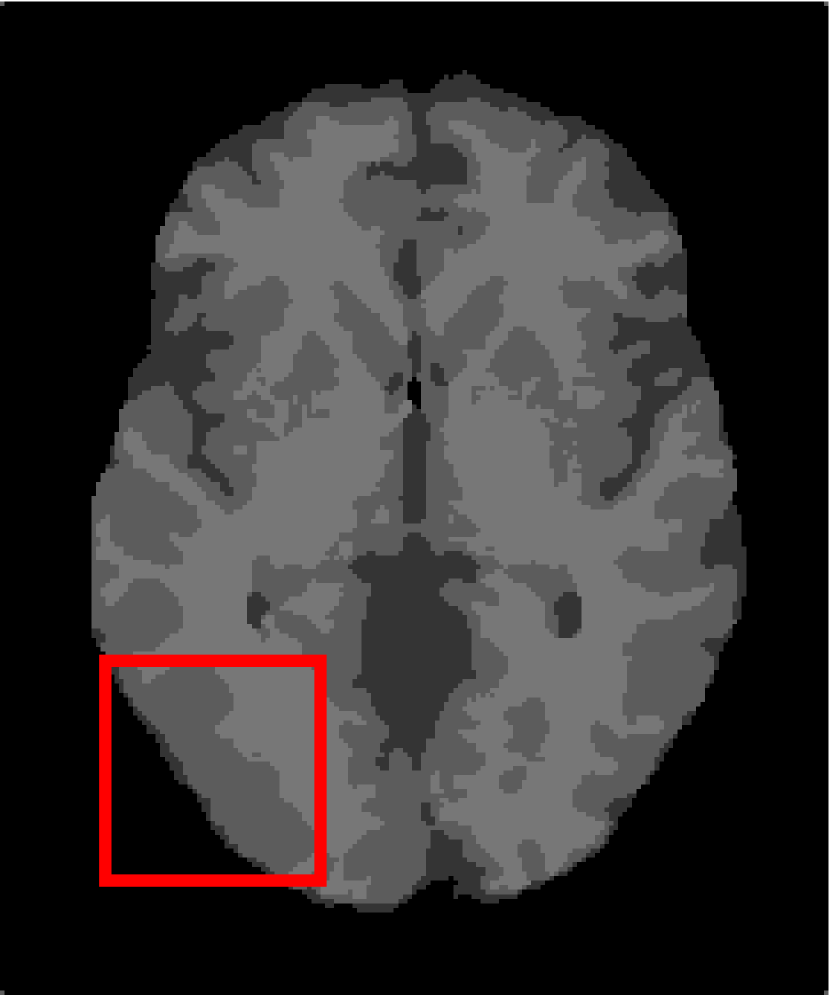

4.4.2 Results on Medical Images

Next, we representatively segment five medical images from BrianWeb. They are represented as five slices in the axial plane with a sequence of 70, 80, 90, 100 and 110, which are generated by T1 modality with slice thickness of 1mm resolution, 9% noise and 20% intensity non-uniformity. Here, we set c=4𝑐4c=4 for all cases. The comparison between WRFCM and its peers are shown in Fig. 9 and Table II. The best values are in bold.

Figure 9: Segmentation results on five medical images. The parameter: ϕ=5.35italic-ϕ5.35\phi=5.35. From top to bottom: noisy images, ground truth, and results of FCM_S1, FCM_S2, FLICM, KWFLICM, FRFCM, WFCM, DSFCM_N, and WRFCM.

TABLE II: Segmentation performance (%) on medical images in BrianWeb

Algorithm Fig. 9 column 1 Fig. 9 column 2 Fig. 9 column 3 Fig. 9 column 4 Fig. 9 column 5

SA SDS MCC SA SDS MCC SA SDS MCC SA SDS MCC SA SDS MCC

FCM_S1 75.756 97.852 96.225 75.026 98.109 96.656 79.792 98.452 97.334 81.887 98.614 97.680 81.869 94.254 90.947

FCM_S2 75.769 98.119 96.664 74.970 98.176 96.765 79.886 98.458 97.338 82.073 98.625 97.695 81.788 98.223 97.195

FLICM 74.998 98.070 96.568 74.185 98.122 96.660 79.099 98.515 97.432 81.447 98.627 97.691 81.668 98.273 97.260

KWFLICM 74.840 98.259 96.878 73.839 97.860 96.190 79.560 98.453 97.316 81.887 98.482 97.443 81.370 98.297 97.286

FRFCM 75.853 97.620 95.775 75.514 97.660 95.830 80.283 98.278 97.013 81.852 98.319 97.171 81.666 98.079 96.945

WFCM 75.507 97.124 94.957 74.471 97.213 95.045 79.316 97.845 96.283 81.358 97.546 95.211 81.452 95.247 92.501

DSFCM_N 76.400 92.325 86.262 75.288 91.574 85.095 79.861 97.678 95.996 81.831 93.304 88.829 81.750 94.302 91.024

WRFCM 82.317 98.966 98.147 82.141 98.298 96.970 83.914 98.963 98.202 83.533 99.170 98.603 84.615 98.429 97.511

By a view of the marked red square in Fig. 9, we find that FCM_S1, FCM_S2, FLICM, KWFLICM and DSFCM_N are vulnerable to noise and intensity non-uniformity. They give rise to the change of topological shapes to some extent. Unlike them, FRFCM and WFCM achieve sufficient noise removal. However, they produce overly smooth contours. Compared with its seven peers, WRFCM can not only suppress noise adequately but also acquire accurate contours. Moreover, it yields the visual result closer to ground truth than its peers. As Table II shows, WRFCM obtains optimal SA, SDS and MCC results for all five medical images. As a conclusion, it outperforms its peers visually and quantitatively.